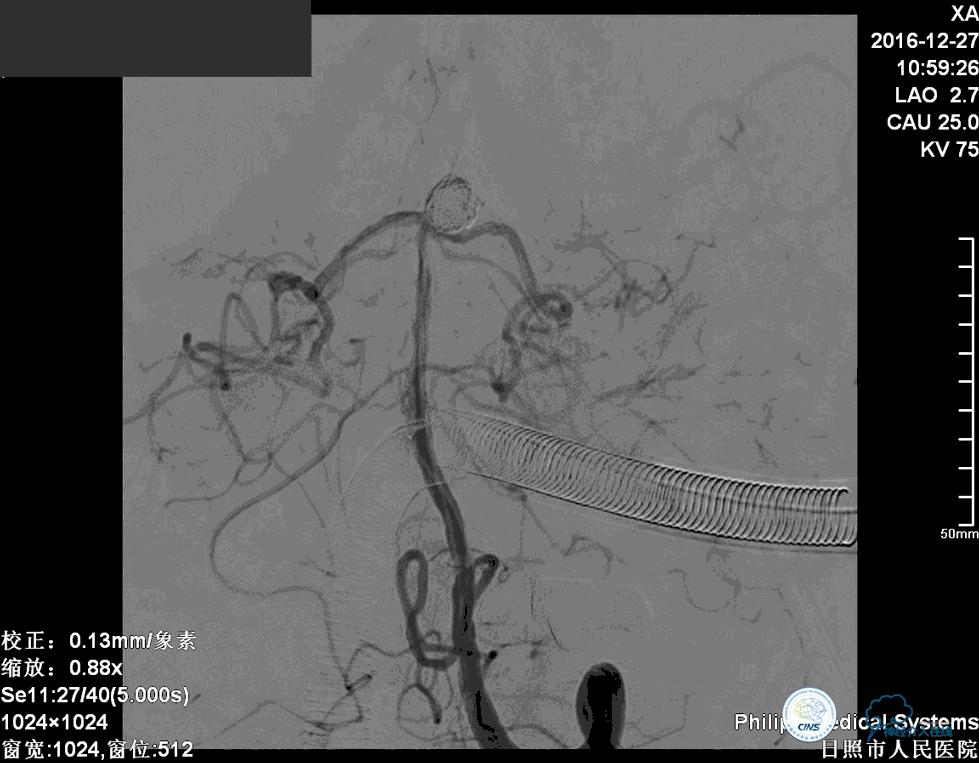

术后患者神志清楚,术后肢体运动较术前未见明显异常。

这个手术的难点是在保证动脉瘤致密栓塞的同时,要保证双侧大脑后动脉的通畅。最终手术达到了较好的效果。

术后患者神志清楚,术后肢体运动较术前未见明显异常。双微管技术降低了患者治疗的费用。同时避免了支架置入以后,终生服用抗血小板药物的情况。